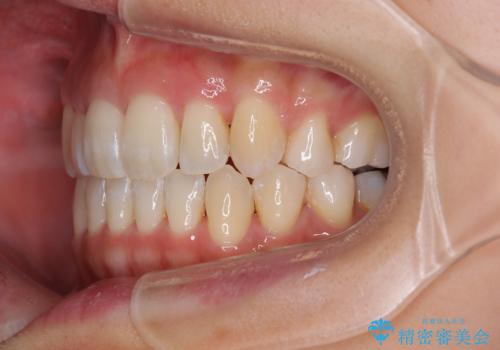

八重歯を改善 ワイヤー装置での抜歯矯正

- 目立つ八重歯を気にして来院された患者様です。

下顎歯列の叢生は軽度であることと、口元の突出感が全くなかったことから、八重歯解消のために上顎左右第一小臼歯を抜歯し、ワイヤー装置にて矯正治療を行うこととしました。

八重歯をスムーズに解消するために、補助装置を用いることで速やかに歯列を整えることができました。